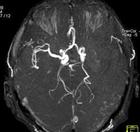

(2)MRI:可清晰显示早期缺血性梗死脑干及小脑梗死静脉窦血栓形成等梗死后数小时即出现T1低信号T2高信号病灶,出血性梗死显示其中混杂T1高信号。钆增强MRI较平扫敏感。功能性MRI弥散加权成像(DWI)可早期诊断缺血性卒中,发病2h内即显示缺血病变为早期治疗提供重要信息。DSA可发现血管狭窄及闭塞部位,显示动脉炎、Moyamoya病、动脉瘤和动静脉畸形等。